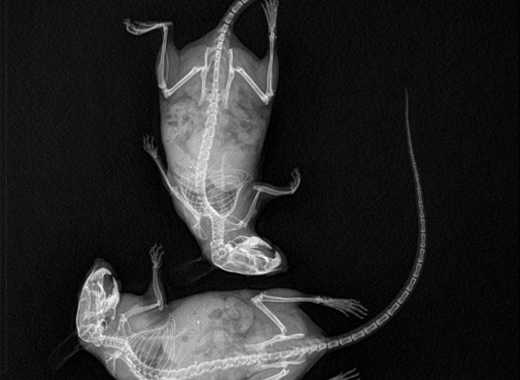

基于平板探測器的小動物微型CT成像系統(tǒng)

1967年,Godfrey N.Hounsfield發(fā)明了世界上第一臺CT設備。能夠從多個角度拍攝X 片,采集被攝物體的三維信息,在不破壞物體的情況下觀察其內部結構。 -